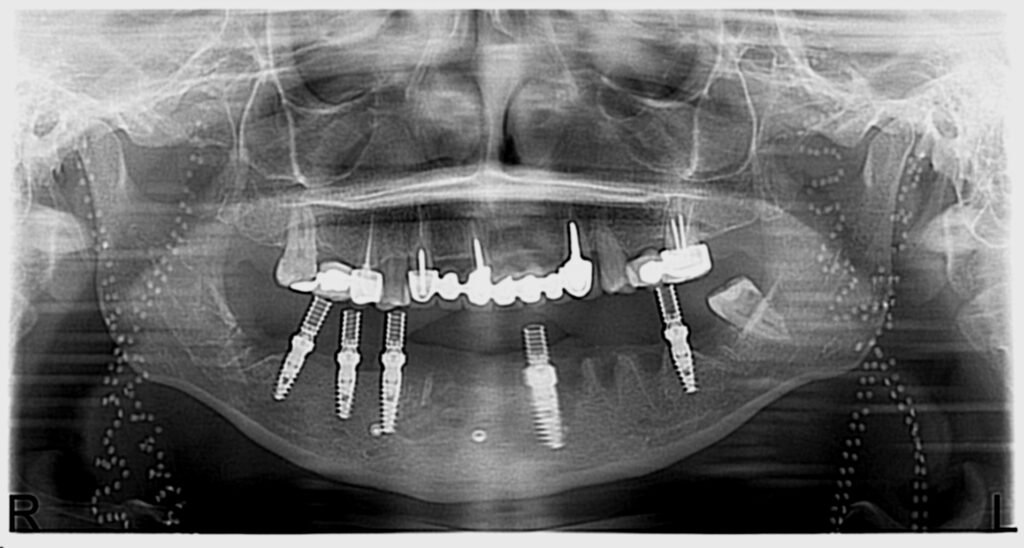

Réhabilitation complète mandibulaire : 4 implants et mise en charge immédiate

Patiente présentant une édentation mandibulaire nécessitant une réhabilitation complète implanto-portée.

Le plan de traitement a consisté en la pose de 4 implants au niveau de la mâchoire inférieure avec mise en charge immédiate, permettant une restauration fonctionnelle et esthétique rapide.

La réhabilitation finale a été réalisée par un bridge complet vissé, garantissant stabilité, confort et maintenance facilitée.